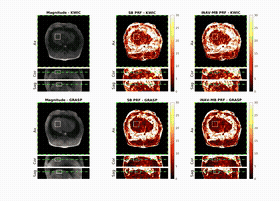

Active electromagnetic interference suppression for MR thermometry during MR-guided microwave ablation

Qing Dai, Jason Chiang, Shu-Fu Shih, Wenqi Zhou, David S. K. Lu, and Holden H. Wu

In Proc. International Society for Magnetic Resonance in Medicine Annual Meeting, 2025

U.S. Patent Pending